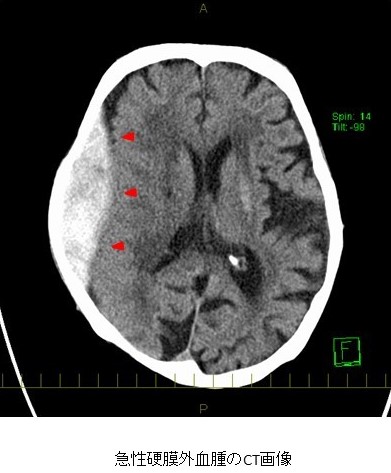

診断にはCTによる画像診断が有用で、頭蓋骨と脳の間の凸レンズ型の高吸収域が特徴的です。